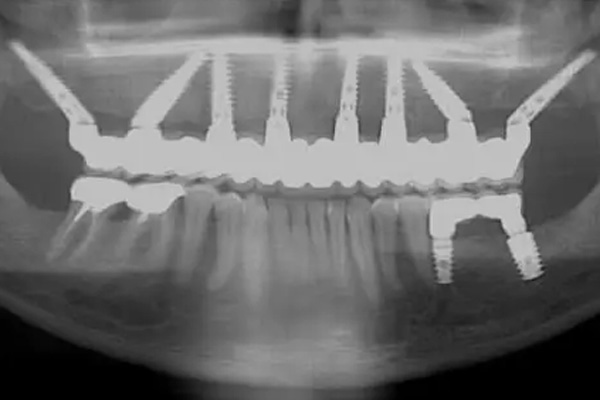

Иногда по решению врача используются 5, 6, 7 или 8 имплантатов. Принцип тот же, что и при All-on-4:

- имплантаты устанавливаются аналогичным образом,

- на них фиксируется единая несъёмная конструкция.

В таких случаях говорят о методах All-on-6 или All-on-8.

Сегодня термин «All-on-4» часто используют как общее название технологий немедленной нагрузки, когда полный зубной ряд фиксируется на нескольких имплантатах — даже если их больше четырёх.